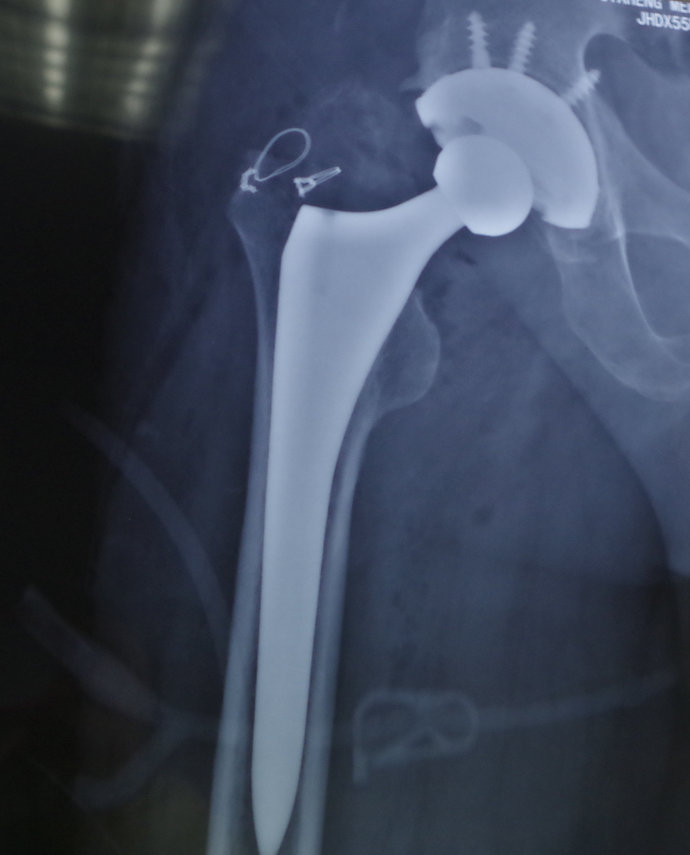

2月21日上午八点,全麻的情况下,由胡玉华院长亲自操刀,为患者行右侧人工全髋关节置换术。由于患者家属的血型与薛先生都不匹配,我院丁荣清医生勇敢的站出来,为患者献血400ml。精神可嘉的他不顾献血后的疲劳,仍参与了手术,手术有条不紊的顺利结束。

髋关节置换术或全髋关节置换术是用人造髋关节置换所有或部分髋关节以重建关节运动功能的一种修复手术。人工关节置换术是用生物材料或非生物材料制成关节假体,植入人体替代病损的关节结构的一类手术方法,其目的是消除疼痛,矫正畸形,重建一个稳定的关节而恢复和改善关节的运动功能。